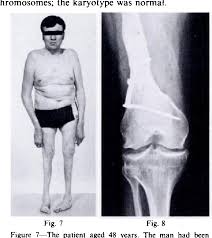

Figure 7 From Congenital Contractural Arachnodactyly Report Of A Case And Of An Operation For Knee Contracture Semantic Scholar